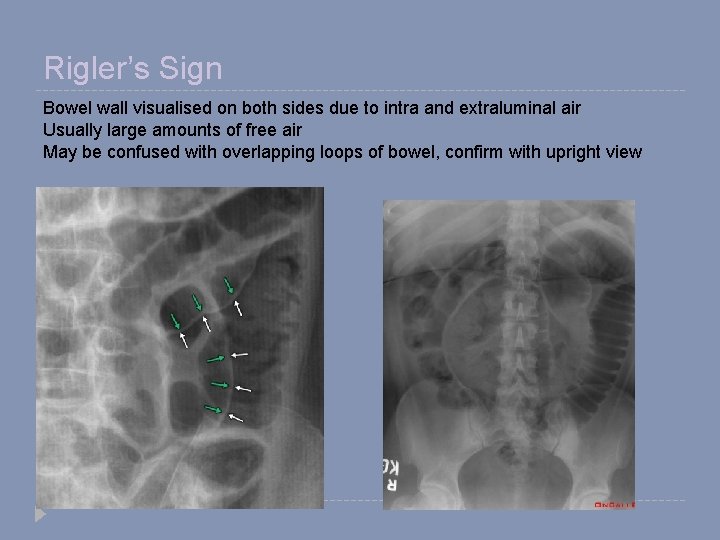

Rigler’s Sign Bowel wall visualised on both sides due to intra and extraluminal air Usually large amounts of free air May be confused with overlapping loops of bowel, confirm with upright view